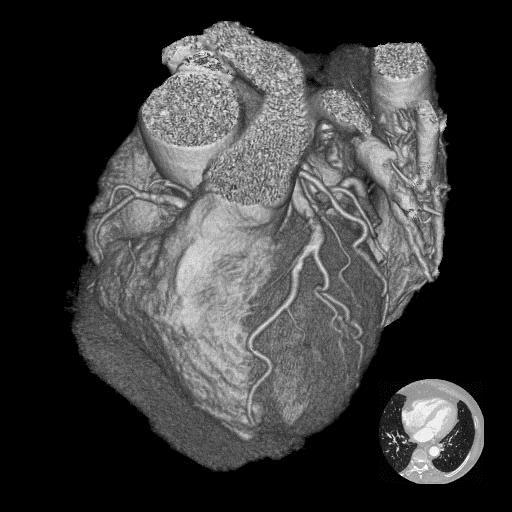

Анатомия коронарных артерий: КТ-изображения